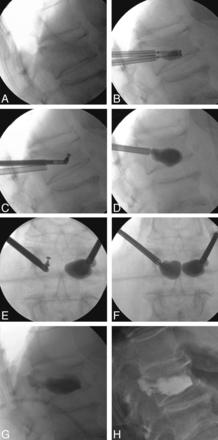

Figure 7 is an illustrative case in curette and balloon use; the 71-year-old female patient had a nonmobile L1 fracture and was randomized to the IBTF group. The initial balloon inflation was poor and had an irregular inflation pattern (1.0 mL and 230 PSI, bilateral). After bilateral curette use and a second balloon inflation, the result was a more uniform fill (230 PSI, bilateral; and 2.5 [right] and 3.0 mL [left]); however, the degree of vertebral body angulation correction was minimal overall (0.2°).

Case illustration of nonmobile fracture and use of curette. A, Intraoperative postural reduction with a bolster. B, Intraoperative first balloon inflation. C, Intraoperative curette usage (used bilaterally but image shows use only on 1 side). D, Intraoperative second balloon inflation. E, Anteroposterior (AP) film of C. F, AP film of D. G, Intraoperative cement placement. H, Postoperative standing x-ray.